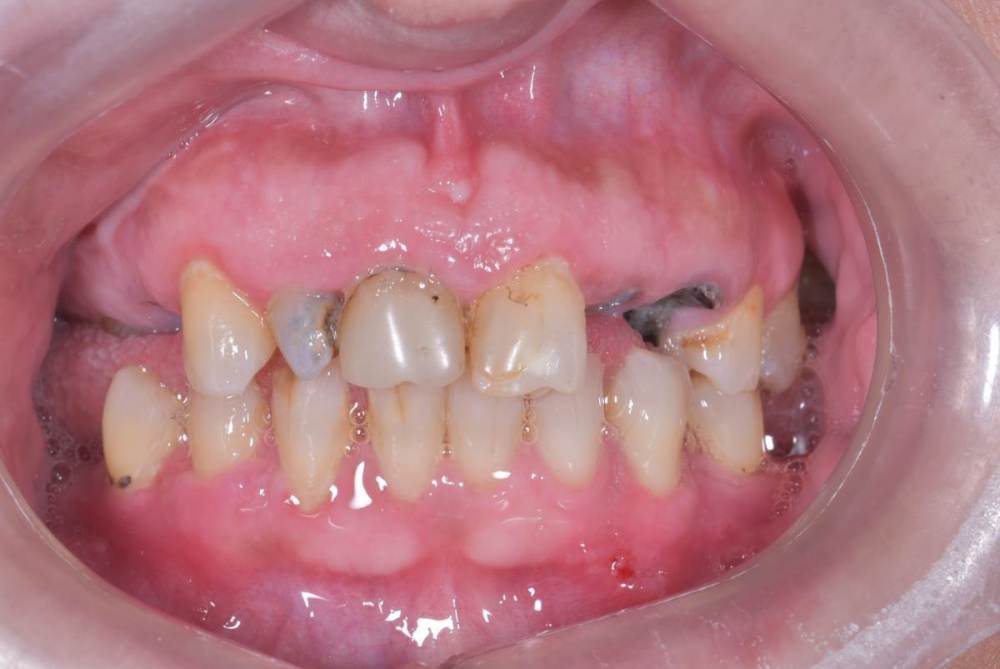

TIGER Опубликовано 3 ноября, 2023 Поделиться Опубликовано 3 ноября, 2023 Периохирургия способна на чудеса)не спешите удалять зубы 5 1 Ссылка на комментарий